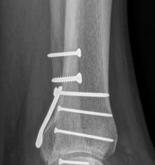

We review everything you need to understand about Partial Articular Fractureplate Fixation: Restore Anatomy. Partial articular fractureplate fixation addresses displaced intraarticular fractures, particularly those of the posterior distal tibia, to restore anatomical congruity and joint function. This open reduction internal fixation procedure often employs buttress plates to stabilize the fracture, ensuring proper length, alignment, and rotation for weight-bearing joints. This approach is crucial for complex ankle injuries.

Partial articular fractures, classified under the AO/OTA alphanumeric system as Type B fractures, represent a complex subset of orthopedic injuries where a portion of the articular surface is disrupted while the remainder of the joint remains in continuity with the metaphyseal and diaphyseal regions. The fundamental objective in the surgical management of these fractures is the restoration of articular congruity and the provision of absolute stability to permit early, active mobilization. Unlike extra-articular or diaphyseal fractures where relative stability and secondary bone healing via callus formation are acceptable, partial articular fractures demand anatomic reduction and primary bone healing to mitigate the risk of post-traumatic osteoarthritis.

Historically, the management of these injuries was fraught with complications, including joint stiffness, malunion, and rapid chondral degeneration secondary to prolonged immobilization. The paradigm shifted dramatically with the establishment of the Arbeitsgemeinschaft für Osteosynthesefragen (AO) principles. The contemporary approach emphasizes meticulous soft tissue handling, direct visualization of the articular surface, interfragmentary compression utilizing lag screws, and the application of a buttress or neutralization plate to counteract axial, shear, and torsional forces.